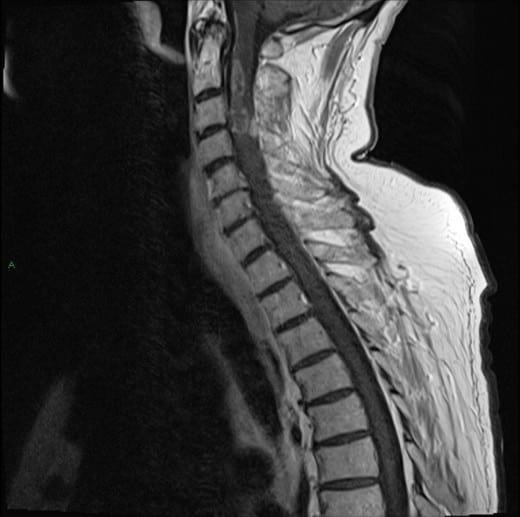

U tủy sống

» Thông tin: Nam giới – 70 tuổi.

» Lâm sàng: Yếu vai phải.

# U sao bào tủy sống (Spinal Astroctyoma) ngang mức C2-C4.